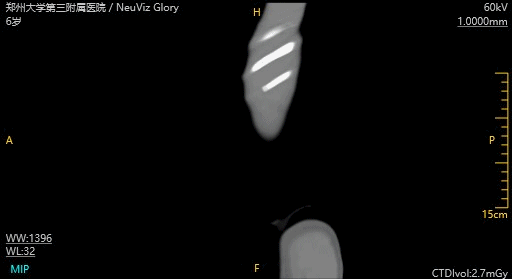

6岁儿童,间断腹胀5天

CT腹部平扫:胃腔扩张,腹部肠管积气扩张,盆腔可见一囊状低密度影,边界

不清

诊断:盆腔囊性低密度影,包裹性积液,建议CT增强扫描;胃腔扩张,肠胀气

扫描参数:

60kV,自动mAs

CTDIvol: 2.7mGy

DLP: 33.9mGy*cm

ED: 0.509mSv(k=0.015)